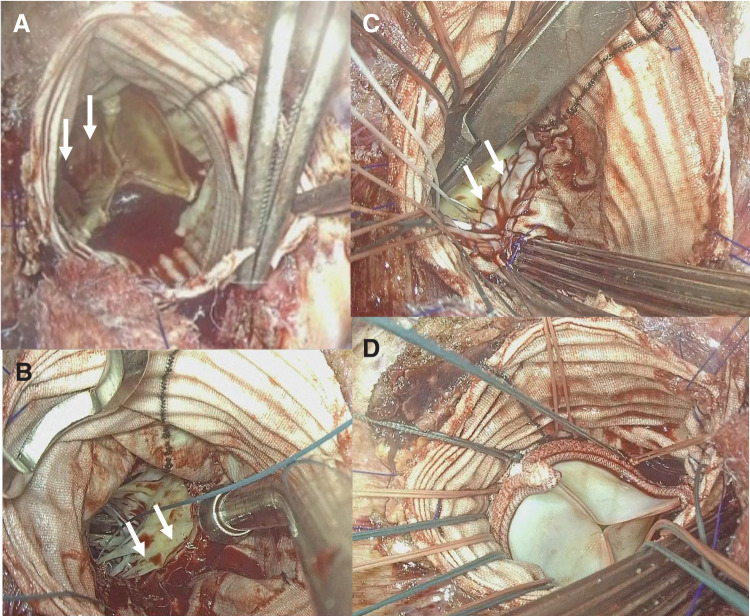

Case presentation: Here, we report 3 cases of prosthetic valve endocarditis following the Bentall procedure, a common ARR technique, in older patients (mean age: 73.7 ± 3.5 years). All preoperative blood cultures were negative, and no signs of prosthetic graft infection were noted on CT. Due to advanced frailty (Clinical Frailty Scale scores of 7 or 8), conventional redo-ARR was deemed prohibitively high-risk. Risk assessment using the JapanSCORE showed a mean predicted mortality of 32.5% ± 21.0%, with combined mortality and morbidity of 63.7% ± 22.9%. Instead of redo-ARR, annular reconstruction using a bovine pericardial patch was performed, followed by redo aortic valve replacement. All patients underwent successful surgery with no postoperative reinfection. One patient required prolonged intensive care and was transferred to another facility for rehabilitation, while the other 2 recovered uneventfully and were discharged. During a mean follow-up of 26.3 ± 17.6 months, 2 patients died due to non-cardiac causes: one from pneumonia and the other from gastric cancer.